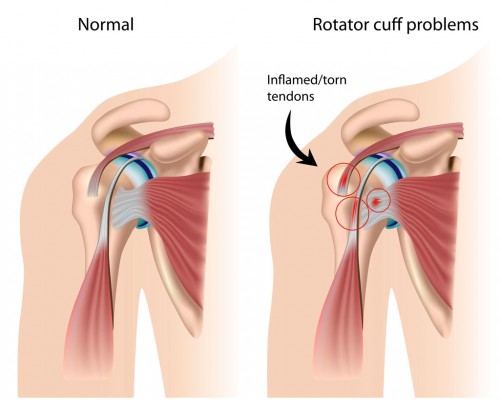

Sciatica

Understanding Sciatica: Causes, Symptoms, and Treatment Options Sciatica is a